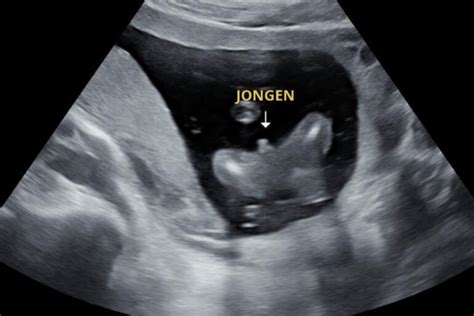

Geslachtsbepaling

Tegenwoordig kan er vanaf de 13e week van de zwangerschap bij het Pretecho Centrum het geslacht van de baby met 75% zekerheid worden bepaald. Deze voorspelling wordt gedaan door middel van de NUB-theorie. Tijdens deze periode heeft uw kindje een soort uitsteekseltje (NUB) tussen de benen. Aan de stand van dit uitsteeksel kan worden gezien of het een jongen of meisje is.

Onze verloskundigen Lichelle en Eveline bieden deze pretecho's aan in ons gezamenlijk Pretecho Centrum. Ook bestaat er natuurlijk de mogelijkheid om vanaf de 16e zwangerschapsweek het geslacht van de baby met zekerheid vast te stellen. Ook dit kan in het Pretecho Centrum middels de geslachtsbepalingsecho.